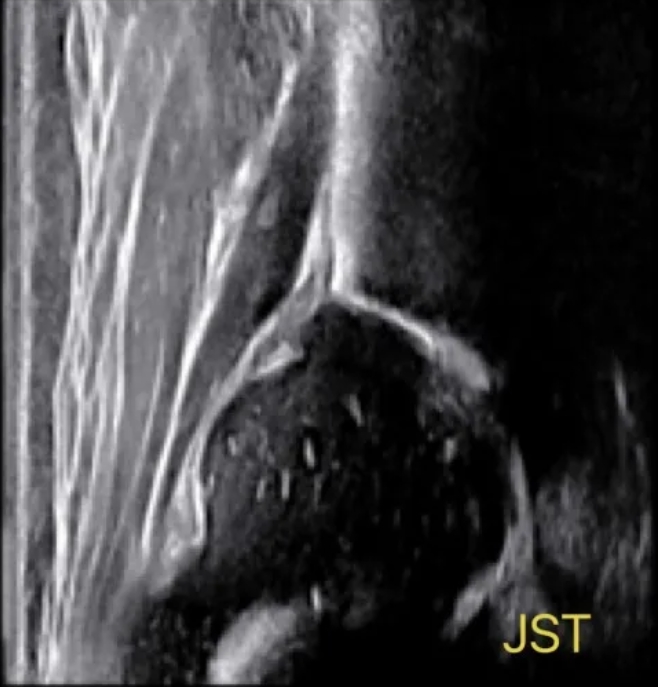

3.2 关节疾病的“守护者”

关节是肌骨超声的另一个重要应用领域。通过肌骨超声,医生可以观察关节的滑膜、软骨、关节囊等结构,对于早期诊断关节炎、滑囊炎等疾病提供了有力的工具。

超声引导骨肉瘤介入诊疗

而且,肌骨介入超声还有一个巨大的优势,那就是它的实时性和动态性。在治疗过程中,超声医生可以实时观察到治疗区域的变化,临床医生参与其中,可以根据需要调整治疗方案,确保治疗的精确性。这种动态的观察和调整,是传统静态影像技术无法比拟的。在我院多年超声科日常工作中,肌骨介入超声与临床专家通力配合,已为患者提供个性化的治疗方案,解决病痛,深受临床医生的肯定和患者的好评。